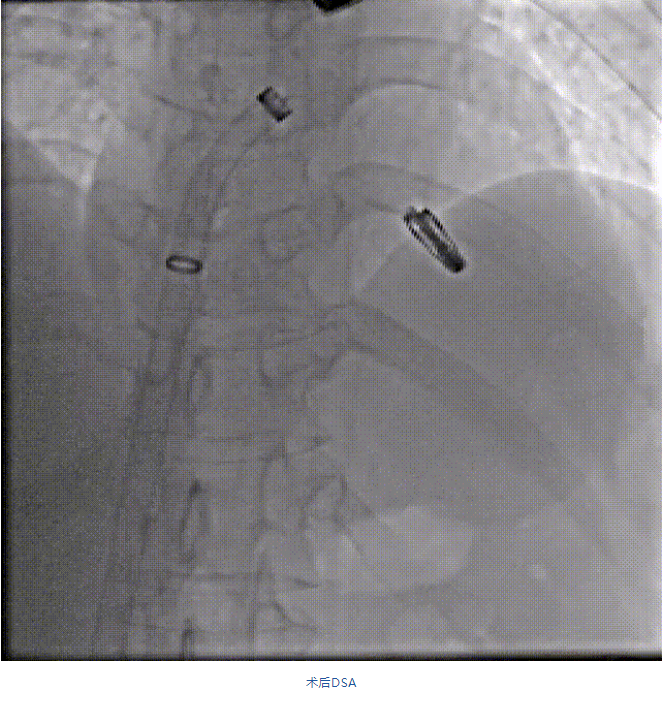

在阜外醫(yī)院潘湘斌教授團隊的支持下,手術經股靜脈-房間隔入路,采用全身麻醉插管,在TEE和DSA引導下完成房間隔穿刺。置入JensClip瓣膜夾系統(tǒng)后,在左房調整瓣膜夾的位置和軸向,后進入左室,在TEE引導下捕捉二尖瓣前后瓣葉,并關閉瓣膜夾。經TEE反復確認手術效果后最終鎖定并釋放瓣膜夾。術后即刻超聲顯示瓣膜夾位置穩(wěn)定,功能良好,二尖瓣反流由術前4+減少至微量,手術圓滿成功。